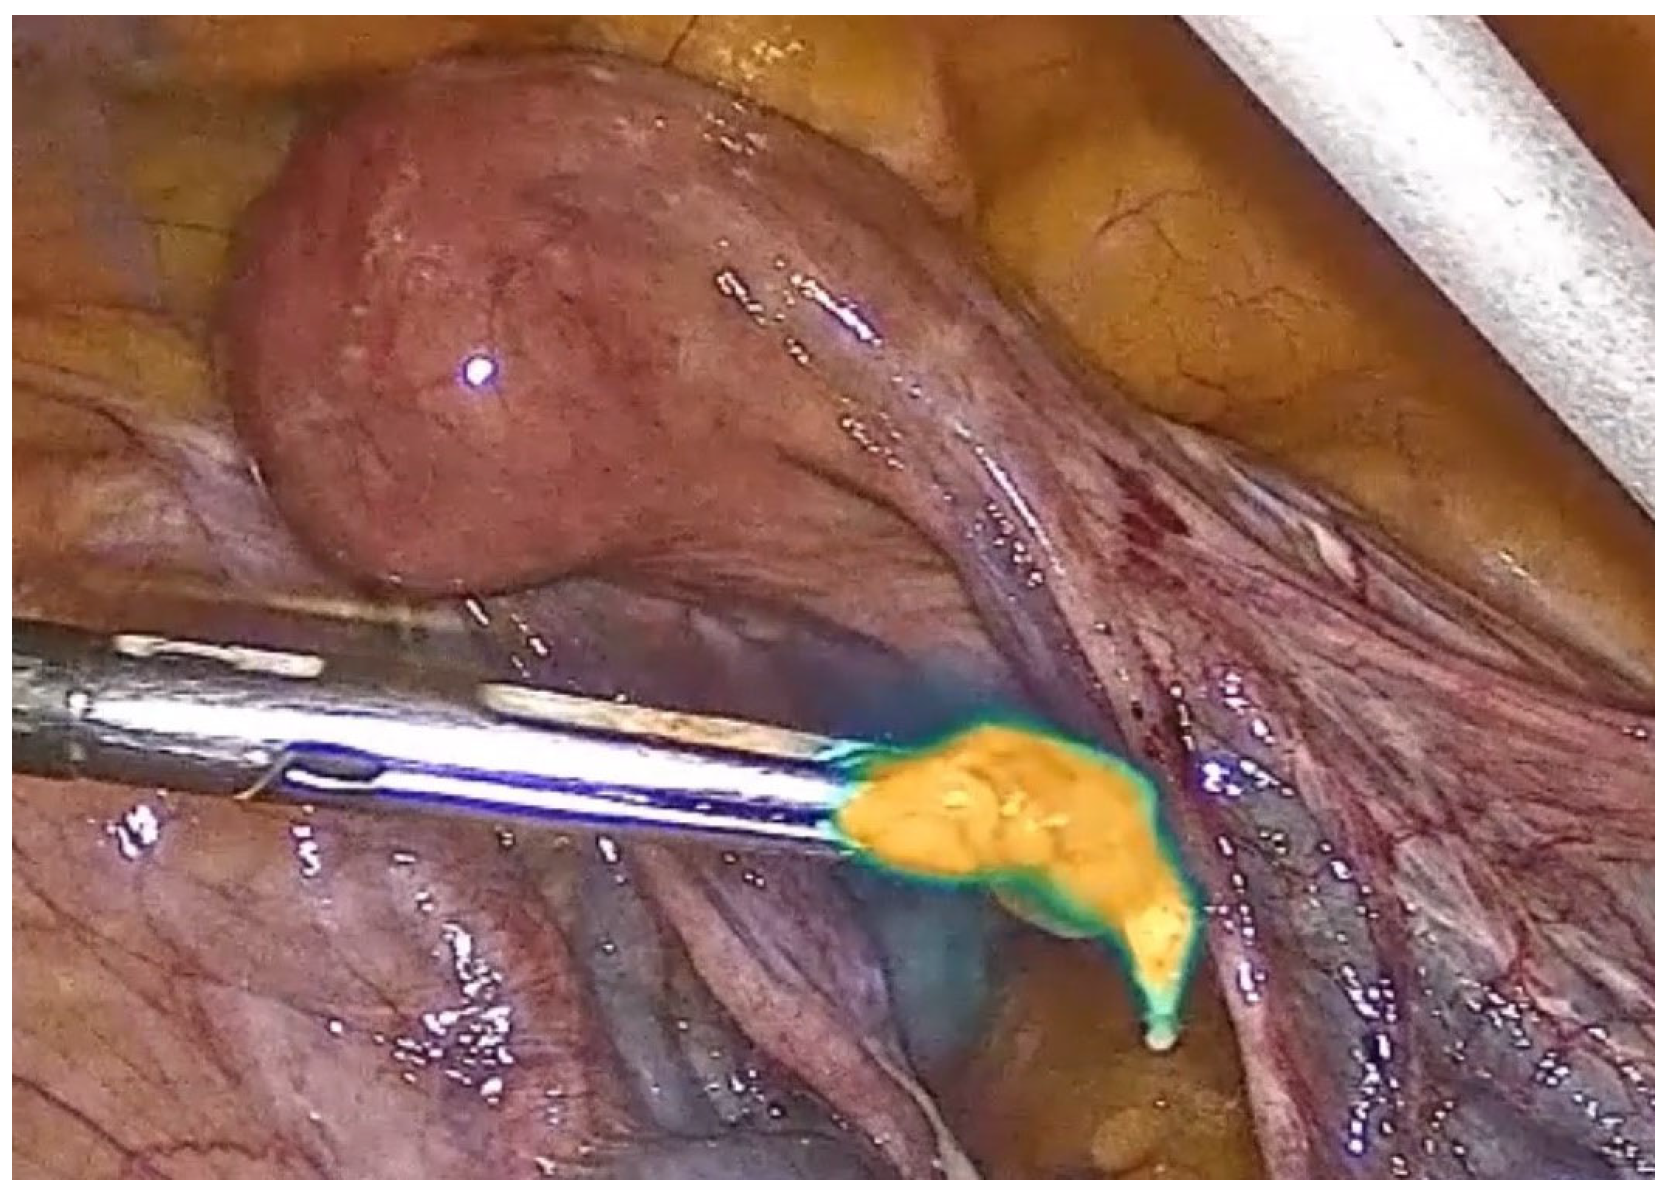

Pelvic Sentinel Lymph Node Biopsy for Endometrial Cancer with Multi-Modal Infrared Signal Technology: A Video Article

2. Presentation of the Case